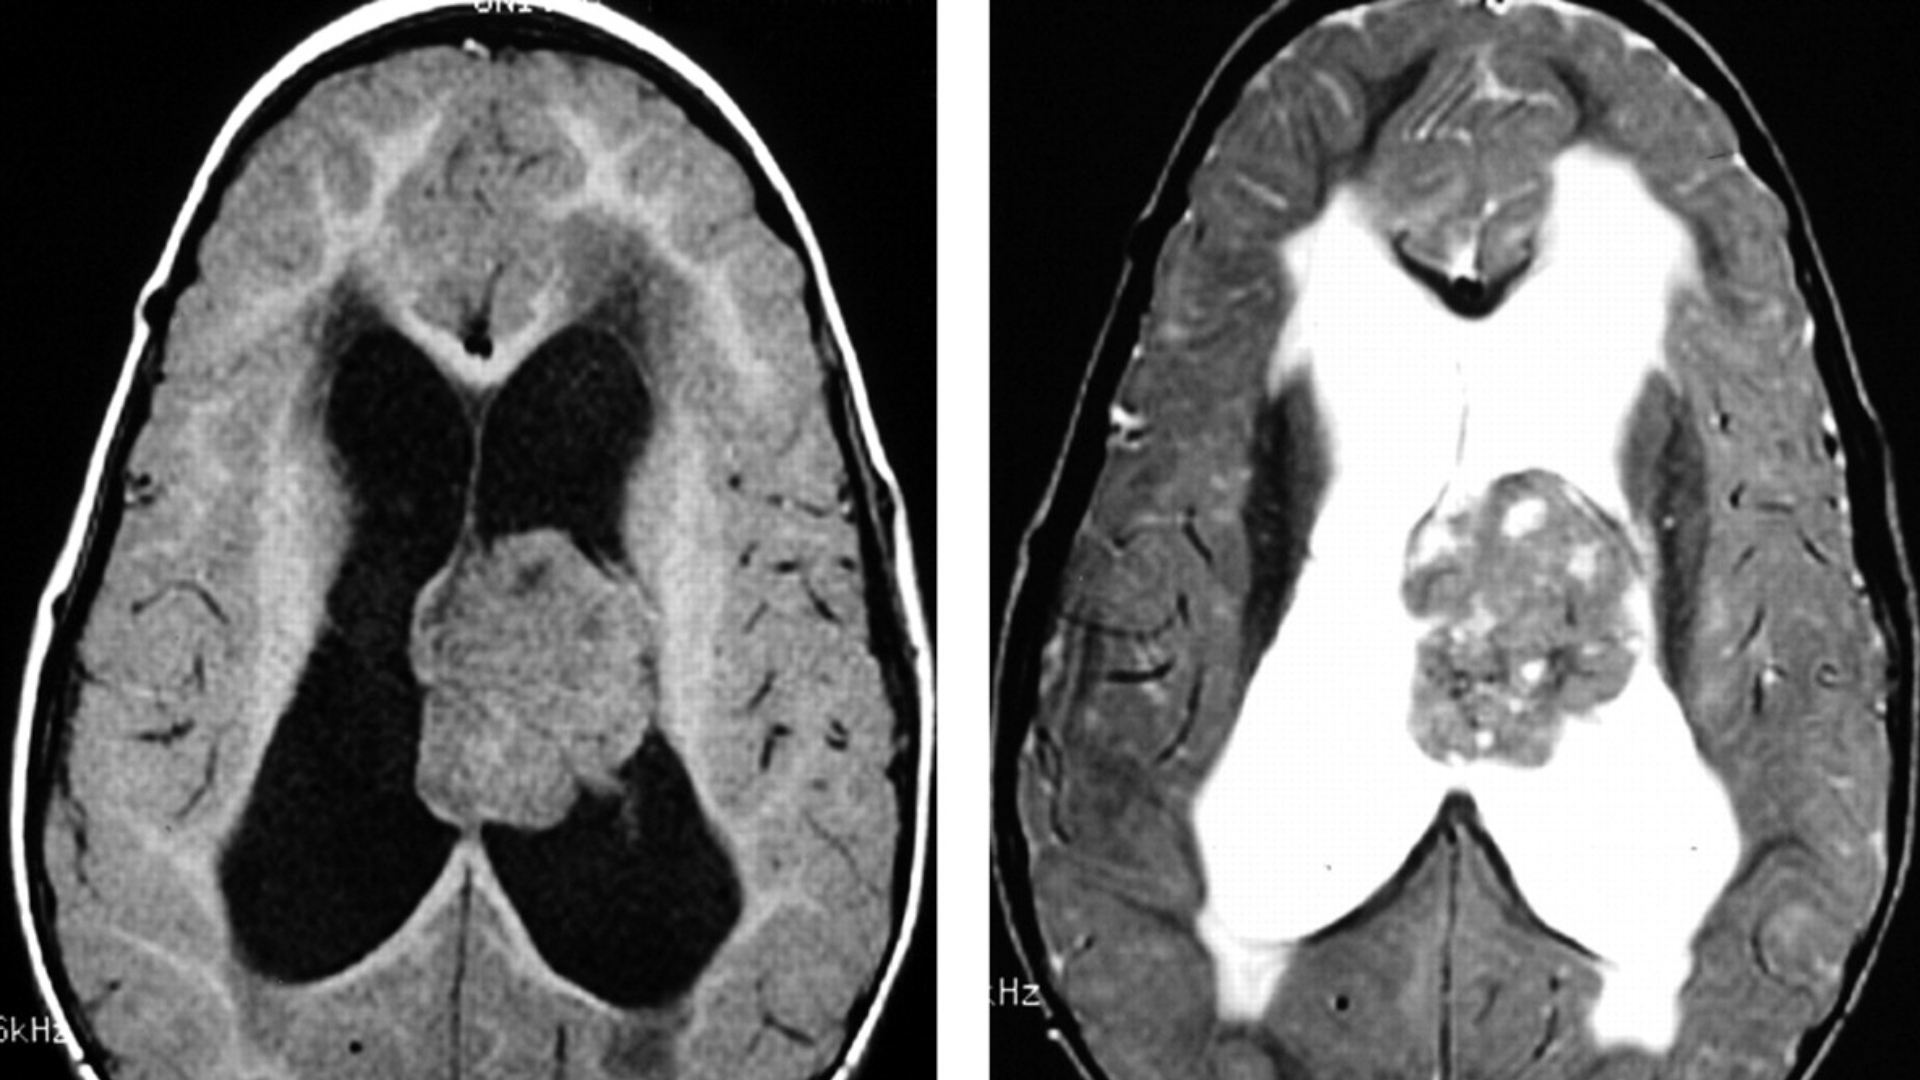

Given ATRT’s aggressive nature and metabolic reliance, early detection becomes crucial. Regular genetic screenings and advanced diagnostic imaging techniques are highly recommended, particularly in high-risk groups, to facilitate prompt intervention.

• Advanced Diagnostics: State-of-the-art imaging (e.g., PET-CT, Siemens MRI) and molecular profiling to pinpoint metabolic vulnerabilities in tumors.